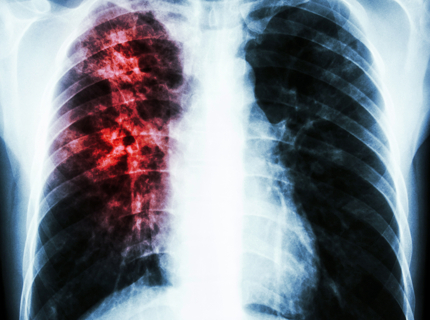

Как определить туберкулез на ранней стадии